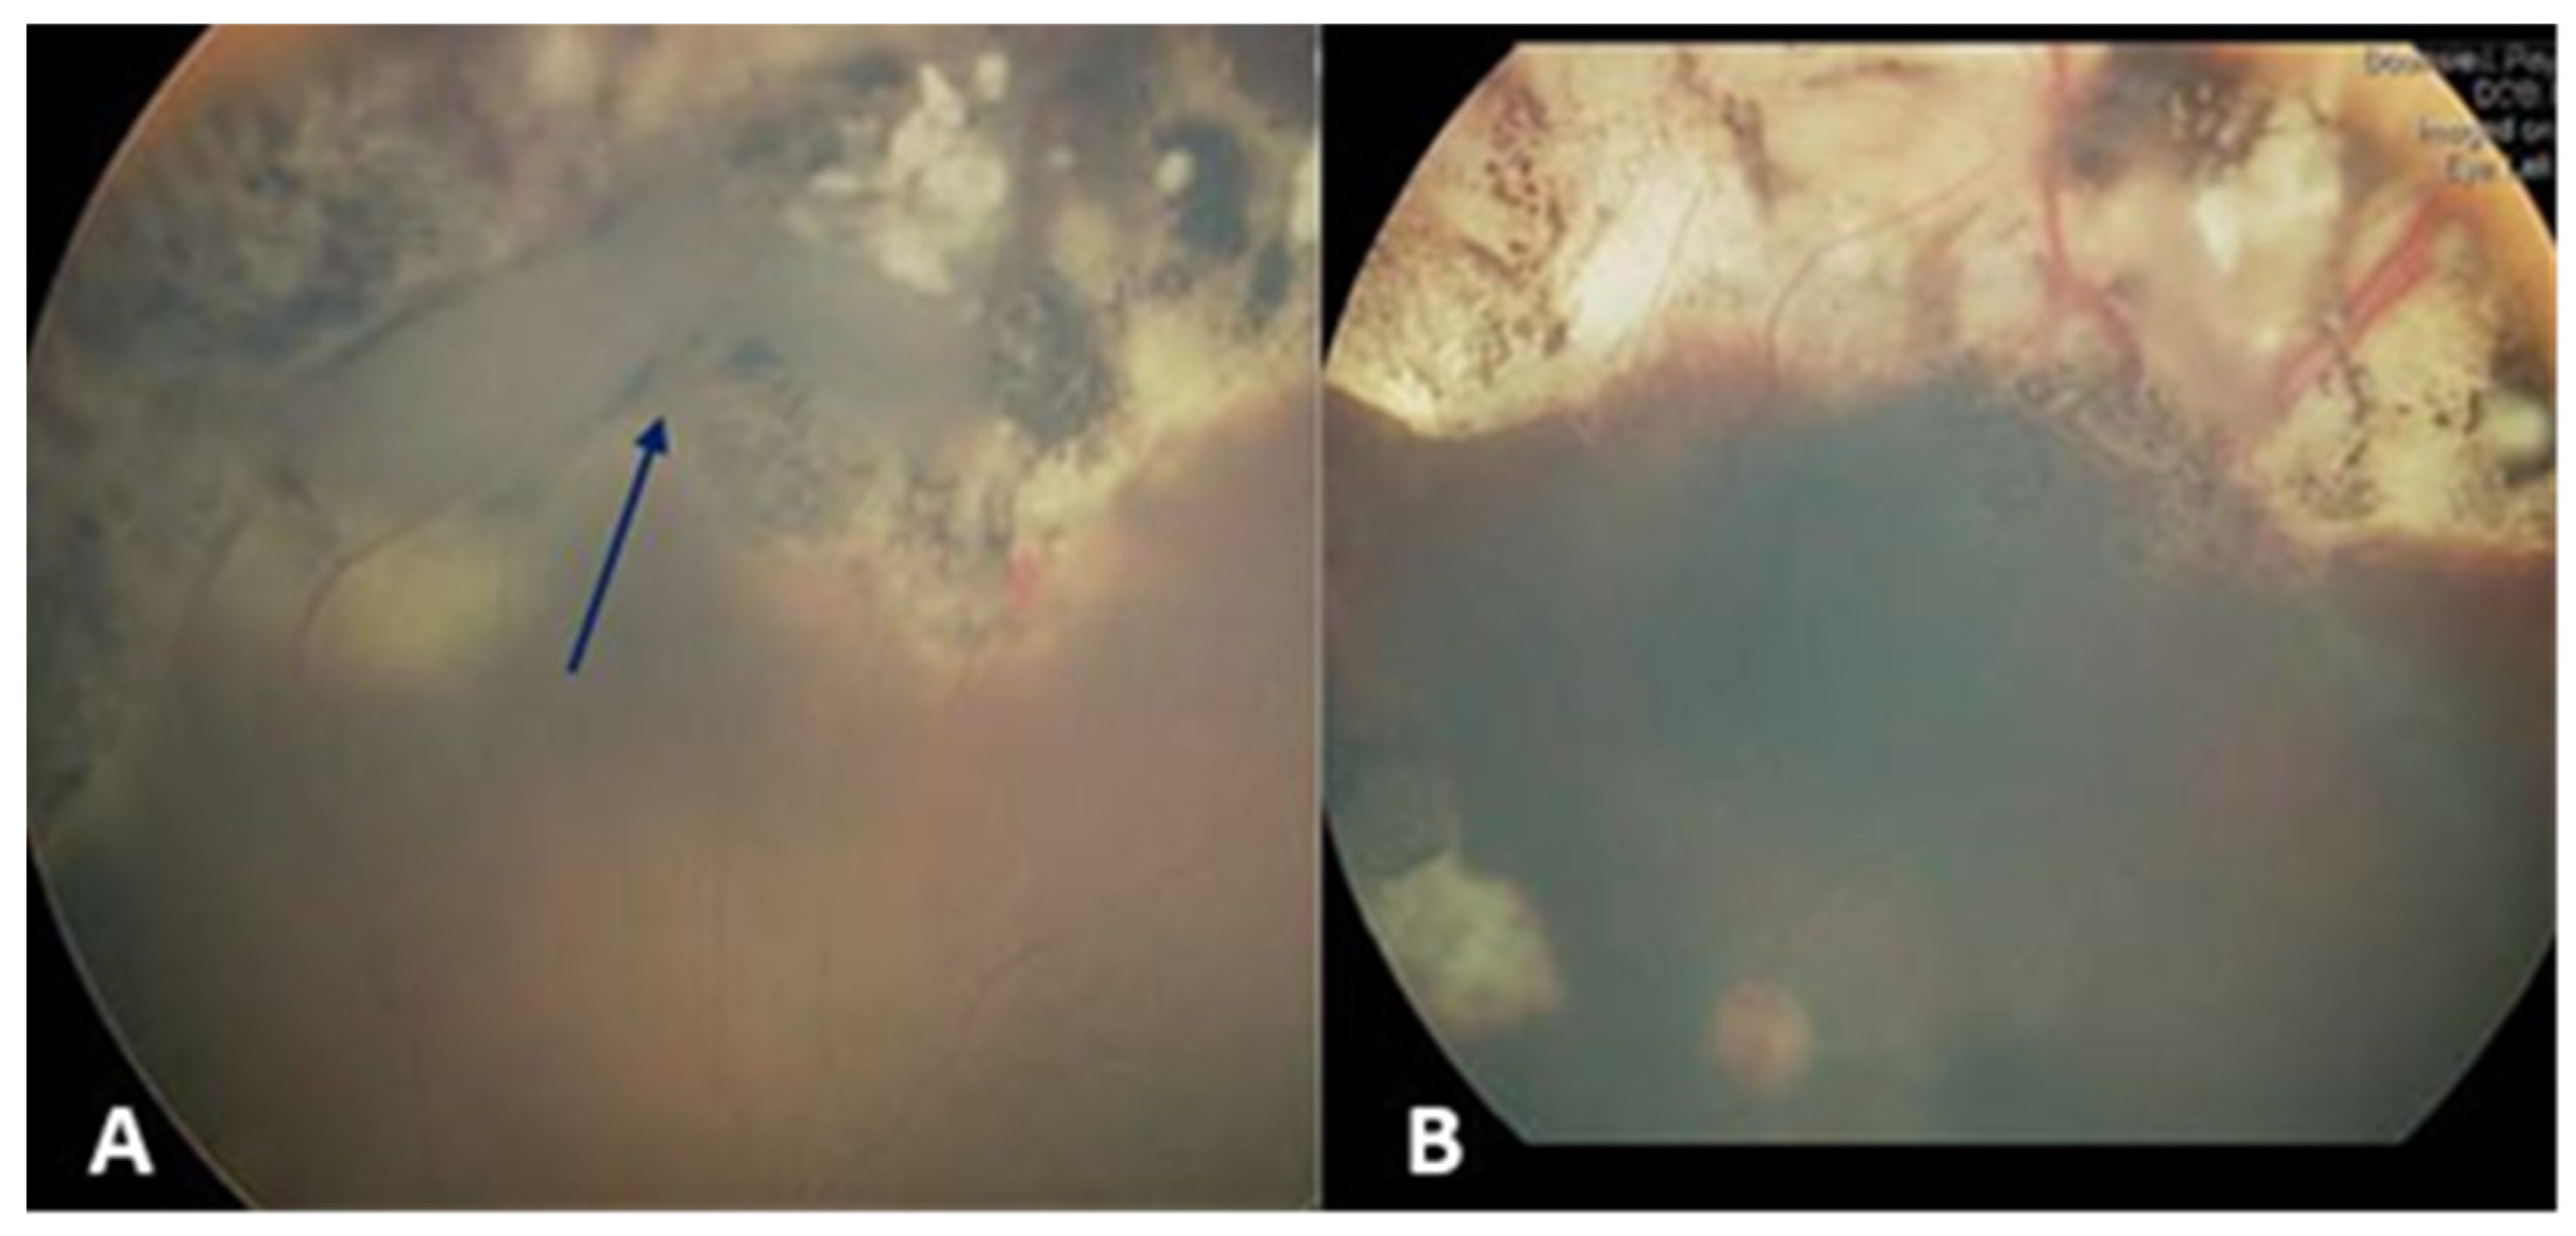

Four weeks after the fourth subtenon injection, he developed subtotal RRD, and a retinal break was identified at the margin of the calcified superior tumor (

Figure 1A). Scleral buckling and retinopexy of the retinal break were implemented for retinal repair. The retina was reattached within three weeks, and the remaining retinal tumors were treated with four further TTT sessions (

Figure 1B). Over an eight-year follow-up period post-surgery, there has been no evidence of tumor reactivation or metastases, and the patient’s best corrected visual acuity was 6/12 at the most recent examination.